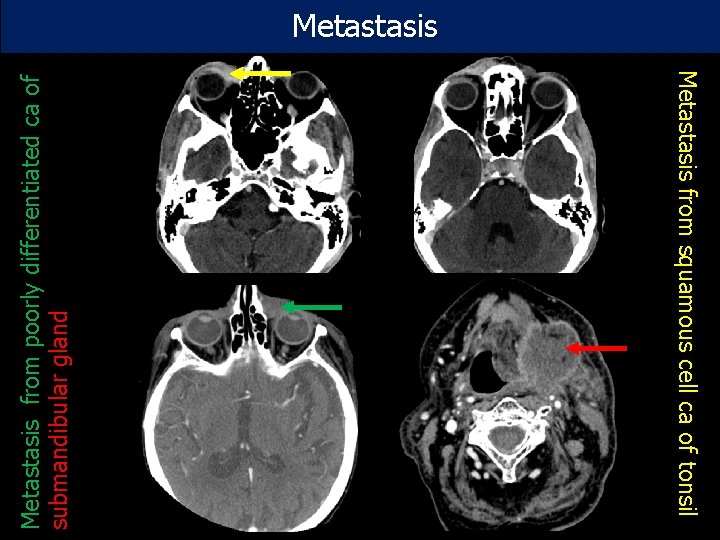

Metastasis from squamous cell ca of tonsil Metastasis from poorly differentiated ca of submandibular gland Metastasis